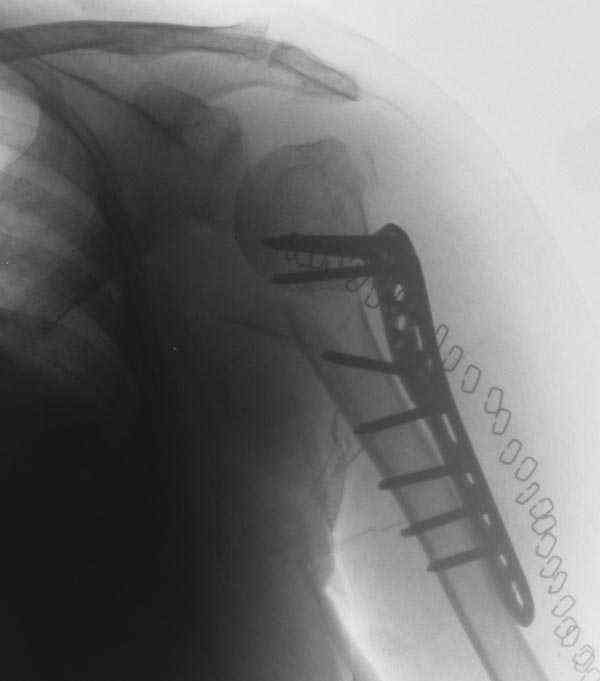

Another option could be closed nailing, see an example, the surgery was done 2 days ago. In common such surgeries are performed under regional anesthesia, not general.

I am attaching the radiographs of the mother of a doctor. She has chronic renal failure for >10 years, diabetes mellitus and coronary artery disease. Age 62. She was offered the options of non-surgical management in a sling and surgery with a locking plate. She was given Tramadol for pain relief. Five days after injury, patient requested surgery, because of pain, inability to move without pain.

The reduction is not perfect. The patient is very small made, and it was difficult to bring the plate proximally without impingement in abduction.

Pain relief after surgery was early and sustained.

I agree that this reduction is not perfect. The gap may later result with nonunion. Such or even better reduction can be reached without site

opening as you mentioned. Locking plates are positioned as less invasive, why so long incision was - even longer than plate?